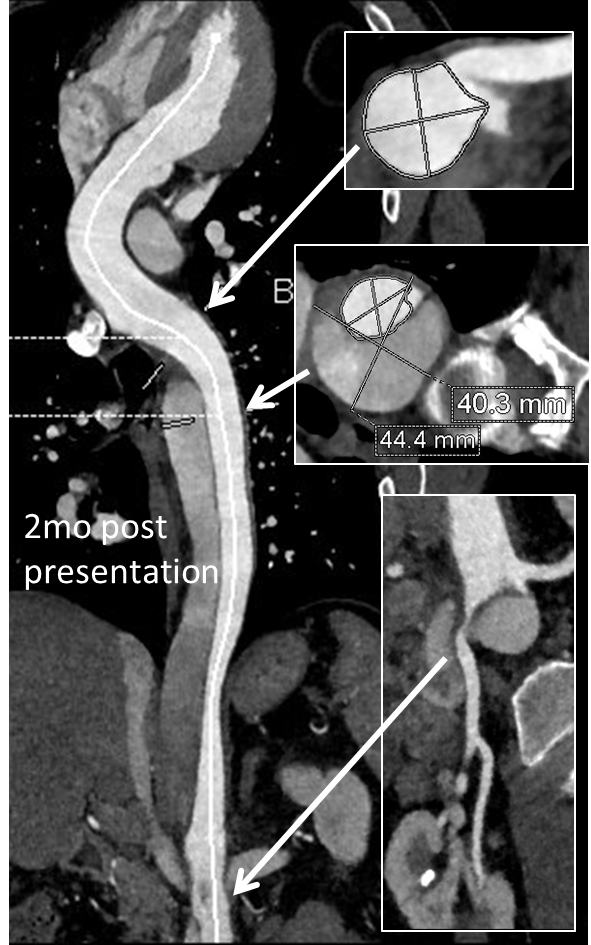

This patient needed a left subclavian artery debranching and then TEVAR of his dissecting thoracic aortic aneurysm, and intervention on his right renal artery. We did this in one setting performing first a left carotid subclavian artery transposition and then percutaneous TEVAR from the left common carotid artery origin to the supraceliac abdominal aorta.

The completion aortography showed good deployment of the CTAG device from the left common carotid artery origin to the celiac axis origin. The false lumen was no longer visualized. The right renal artery which was narrowed was treated with a balloon expandable stent.

The distal thoracic aorta, the true lumen was constrained by a chronic dissection flap. It is here I gently dilate the distal thoracic stent graft with the hopes of eliminating the distal false lumen. This is different from the acute dissection where I rarely balloon.

The TEVAR was done percutaneously, minimizing the overall time in the operating room. The technical details of the transposition can be found in the excellent paper by Dr. Mark Morasch.

When I do this procedure for acute dissection, I quote the patient a general risk of stroke, paralysis of about 2-5% and death of 1-2 percent for someone with low cardiopulmonary risk like this patient had. He recovered rapidly and went home post op day 5.